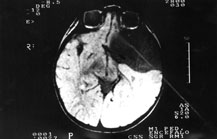

A MRI to the brain showed the presence of a large cystic cavity to the left temporofrontal region with compression of the frontal and temporal lobe and contralateral midline displacement.

Veniva eseguita una R.M. encefalo che denotava la presenza di “...una voluminosa cavità cistica a contenuto simil-liquorale in sede temporo-frontale sinistra; il lobo frontale e il lobo temporale appaiono ipoplasici, il ventricolo laterale omolaterale è parzialmente obliterato e la linea mediana è lievemente spostata controlateralmente ...”(fig. 2)